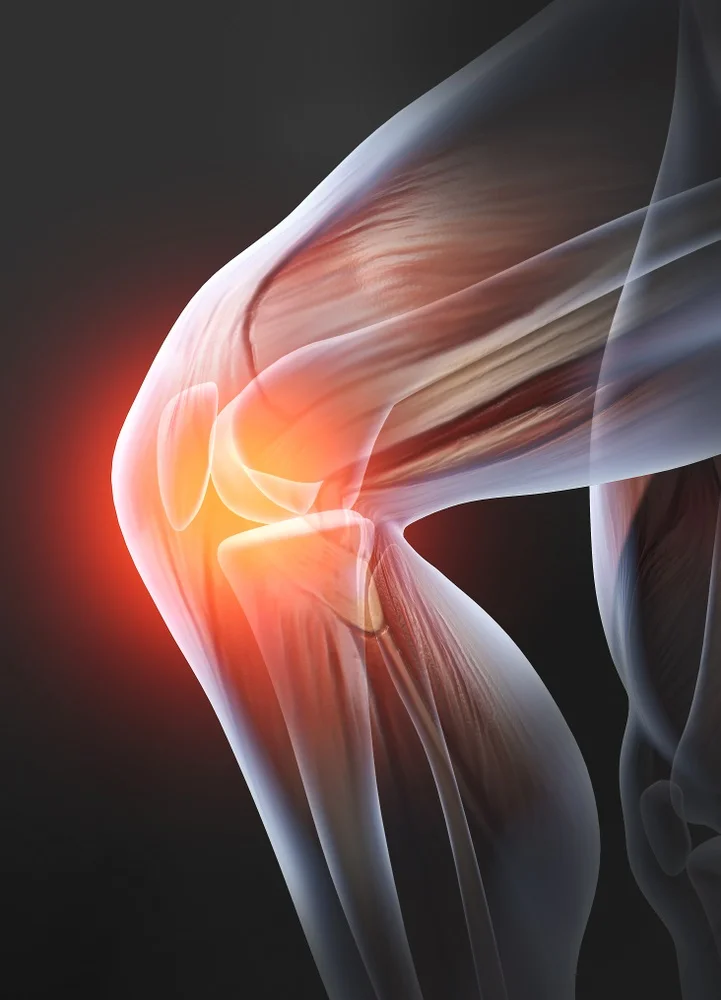

Ο πρόσθιος χιαστός σύνδεσμος βρίσκεται στο μπροστινό μέρος του γονάτου και βοηθάει ώστε να μην γίνεται υπερβολική μπροστινή κίνηση της κνήμης σε σχέση με τον μηρό. Είναι υπεύθυνος για την σταθερότητα του γόνατου και την προστασία του από επιβαρυντικές κινήσεις.

Ο οπίσθιος χιαστός βρίσκεται πίσω από τον πρόσθιο χιαστό και συγκρατεί την κνήμη από οπίσθια ολίσθηση. Η κάκωση του είναι αποτέλεσμα βίαιου τραυματισμού και για αυτό τις περισσότερες φορές συνοδεύεται και από άλλες κακώσεις του γόνατος όπως ρήξη μηνίσκου.